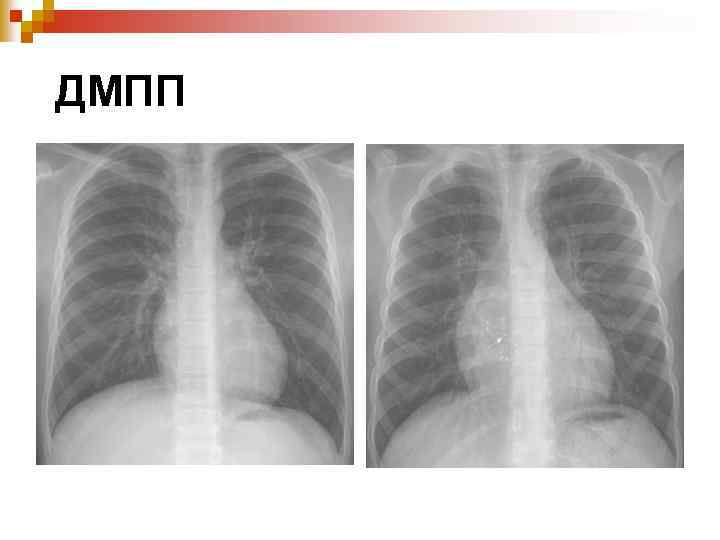

Дефект міжпересердної перегородки

Гемодинамічні порушення

Hemodymamics of ASD SVC IVC Oxygenated blood in PVs ASD shunting ЛП Розширення ПШ ЛШ Застій в легеневій артерії Аортальний викид ↓ Pul. Circulation congestive Недостатність кровообігу Pul. Arterial Hypertension Obstructive PAH Eisenmanger’s syndrome

ЕКГ n Гіпертрофії правого шлуночка (RVH) Правий Кут нахилу осі Блокада правої ніжки пучка Гіса ДМПП

ДМПП